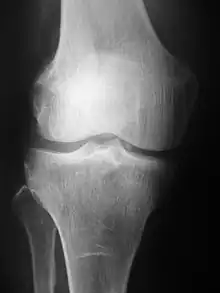

Plain radiography was the only imaging modality available during the first 50 years of radiology. Due to its availability, speed, and lower costs compared to other modalities, radiography is often the first-line test of choice in radiologic diagnosis. Also despite the large amount of data in CT scans, MR scans and other digital-based imaging, there are many disease entities in which the classic diagnosis is obtained by plain radiographs. Examples include various types of arthritis and pneumonia, bone tumors (especially benign bone tumors), fractures, congenital skeletal anomalies, and certain kidney stones.

Mammography and DXA are two applications of low energy projectional radiography, used for the evaluation for breast cancer and osteoporosis, respectively.